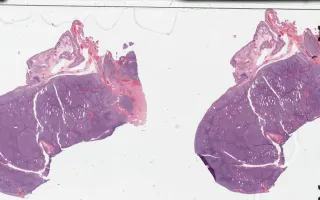

Lymph Nodes, Follicular lymphoma, H&E stain

Sections in this case show effacement of the lymph node architecture by an abnormal lymphoid proliferation with nodular pattern. There is an average of more than 15 centroblasts per 40x high power field amongst centrocytes. The follicular architecture is maintained throughout. No sheeting or clusters of centroblasts are identified.

This slide shows H&E stain. See Related Content for CD20, CD10, BCL6, and BCL2 stains.